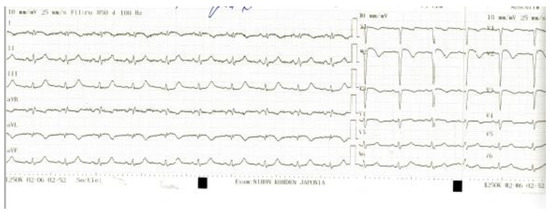

T and Small Protrusion (TAP) Technique in Bifurcations: Coronary Artery Disease in Acute Myocardial Infarction Patients after COVID-19 Pneumonia

Ischemic coronary artery disease in all its forms remains the main cause of death worldwide. Coronary artery bifurcation lesions are a challenge because of their complexity and possible complications. The goal of treating bifurcation lesions is the optimal revascularization of the main vessel without compromising the side branch. Although the study of bifurcation stenting aims to keep the side branch viable, the outcomes regarding major acute cardiovascular events and survivability are related to the optimal treatment of the main vessel. There are many trials that have tried to evaluate the best technique to use with respect to bifurcation lesions, and early studies support provisional stenting as the election treatment. More recent trials highlighted the superior outcomes of the double kissing crush technique used on unprotected distal left main bifurcation lesions. In patients with acute myocardial infarction, two-stent techniques were avoided because of the prolonged procedural time in unstable patients, with high risks of complications. We present the case of a 53-year-old woman with multiple cardiovascular risk factors (dyslipidemia, hypertension, active cancer, post-COVID-19 state) and acute antero-lateral myocardial infarction who underwent primary coronary intervention with the use of the TAP technique for stenting the bifurcation culprit coronary lesion (left anterior descendent artery and first diagonal artery). Full article

Show Figures

Graphical abstract